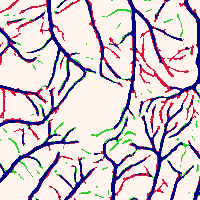

Instead of solely analyzing the signs and magnitudes of the Hessian eigenvalues as in the traditional Frangi filter, we propose to leverage the eigenvectors along with custom-designed magnitudes to create our tensor field as shown in Fig. 3(Left). The core idea of Frangi filter is to enhance the tubular structure by matching the vessel diameter with the distance between the two zero crossings in the second order derivative of Gaussian ( ). However, the solution is not guaranteed to land in range , especially for small vessels. Consequently, we observe that the inaccurate estimation of results in a blurring effect at the vessel boundary, which is problematic for segmentation. As an example in Fig. 3(Left), the direction of at aligns with that at , even though is inside the vessel while is in the background but close to the boundary. This makes it difficult for the vector orientations alone to differentiate points inside and outside the vessel. To tackle this, we introduce the idea of a bipolar tensor by assigning a large magnitude to the orthogonal eigenvector to points in the background, as shown in the blue dashed ellipse. Specifically, we define the magnitudes and associated with the eigenvectors and as:

| (3) |

where is the probability that the intensity of a random pixel in the image is greater than . This is equivalent to normalizing the histogram by the factor and computing the cumulative distribution function at . This term thus provides a normalized brightness function in the range . The exponential term represents how vessel-like the voxel is by using a normalized eigenvalue, and is in the range as well. is a constant that controls the sensitivity, which is empirically set to . With the custom magnitudes and , the two poles can better differentiate vessels from the background. Fig. 3(Right) is an example of BTF on an OCTA image. In practice, we stack the two vectors as the input to the structural encoding network, i.e., .